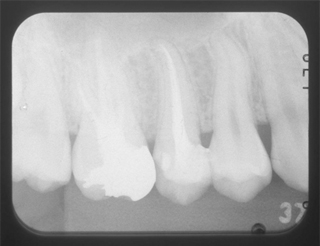

根管と歯のコントラストがはっきり見えません。

それは違う角度から見ると最終的なお薬が緊密に入っていないか、感染歯質を取りきれていないからです。

根のお掃除が不十分で、さらに最終的なお薬とのコントラストがはっきりしておらず、隙間だらけです